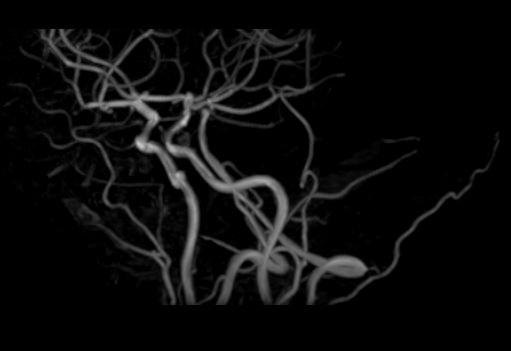

Исследования выполняются на современном высокопольном томографе экспертного класса TOSHIBA VANTAGE TITAN 1,5 Тесла, который использует разные режимы сканирования с толщиной среза от 1мм в различных плоскостях с последующей цифровой обработкой полученных данных для создания трехмерных изображений. МР-ангиография отображает состояние артериальной системы кровоснабжения головного мозга. МР-венография головного мозга позволяет детально изучить особенности венозного русла головного мозга.

Компьютерная программа обрабатывает данные, полученные при сканировании, и формирует объемные изображения как самого мозга, так и сосудистой системы в отдельности без прилегающих тканей. Методики применяются одновременно и взаимодополняют друг друга.

• патология нервов на фоне сосудистых проблем (вазоневральный конфликт — сдавление нерва близлежащим сосудом, также на фоне патологической извитости, аневризмы, сосудистой мальформации).